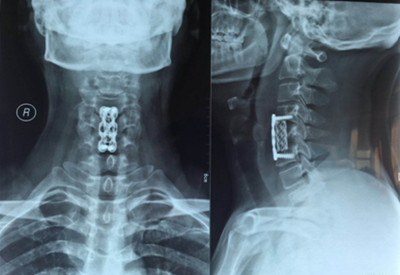

4月23日王先生來院復(fù)查:雙手指麻木感、雙下肢無力感消失,四肢肌肉力量恢復(fù),行走姿態(tài)正常,病情恢復(fù)理想。

圖片三: